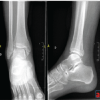

An 82-year-old female patient with a past medical history of osteopenia as well as idiopathic mild mental retardation and dementia presented to a community hospital emergency department (ED) after turning her ankle 24 h before initial evaluation. Initial radiographs demonstrated a trimalleolar ankle fracture without dislocation with a large posterior malleolar fragment as shown in Figure 1.

She was evaluated and placed into a well-padded three-sided splint by the on-call orthopedic resident and instructed to follow up in the orthopedic clinic within the next 5–7 days. Before this injury, the patient was ambulatory about the house and utilized a wheelchair otherwise. At the initial ED visit, she was instructed to remain non-weight bearing and to ice and elevate the extremity to alleviate swelling and pain. Exactly 1 week later, the patient was brought back to the ED due to increased pain to the right ankle. The same orthopedic resident re-evaluated her and noted significant damage to her splint. Radiographs at this point demonstrated that the patient had dislocated the tibiotalar joint while in the splint as shown in Figure 2. Inspection of the skin overlying the right ankle showed the development of serous-filled fracture blisters over the medial and lateral malleoli. The ankle was reduced and splinted by the orthopedic resident, and she was admitted to the hospital for pain control. Discussion with the patient and family revealed that she regularly was kicking a wall with her injured extremity and that they had significant difficulty with keeping her non-weight bearing. A discussion was had with the patient and family regarding treatment options with open reduction and internal fixation versus TTC nail. It was discussed that with TTC nail, there would be closed reduction and relative stability of the fracture with loss of range of motion of the ankle, but that the patient would be able to weight bear post-operatively with lower risk of hardware failure and loss of reduction requiring revision surgery [2].